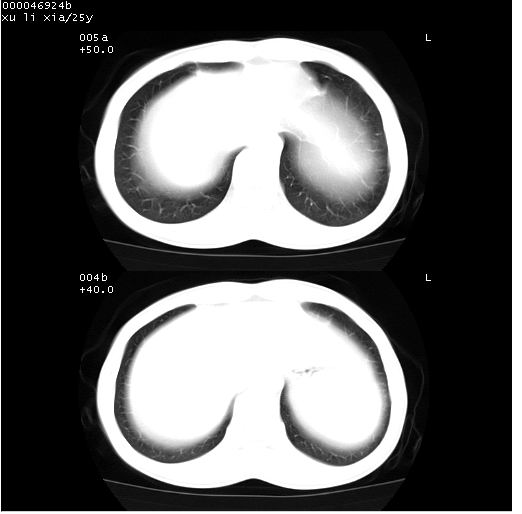

患者 女,25岁。因“左侧卵巢肿瘤”术前胸片偶然发现两肺病变。平素无明显不适,无呼吸系统症状及体征,无传染病史。

cr x线胸片提示:两肺感染性病变(结核可能性大)。

胸部ct轴位平扫(层厚10mm,螺距1.5,重建间隔10mm),图像如下:

(注:上级医院会诊胸部ct片——考虑为肺部真菌感染。)

病灶呈地图样分布于肺外围,与正常组织分界清晰+弥漫性磨玻璃影中见小叶间隔增厚呈碎石路样表现+年轻女性,无明显临床症状=肺泡蛋白沉积症?